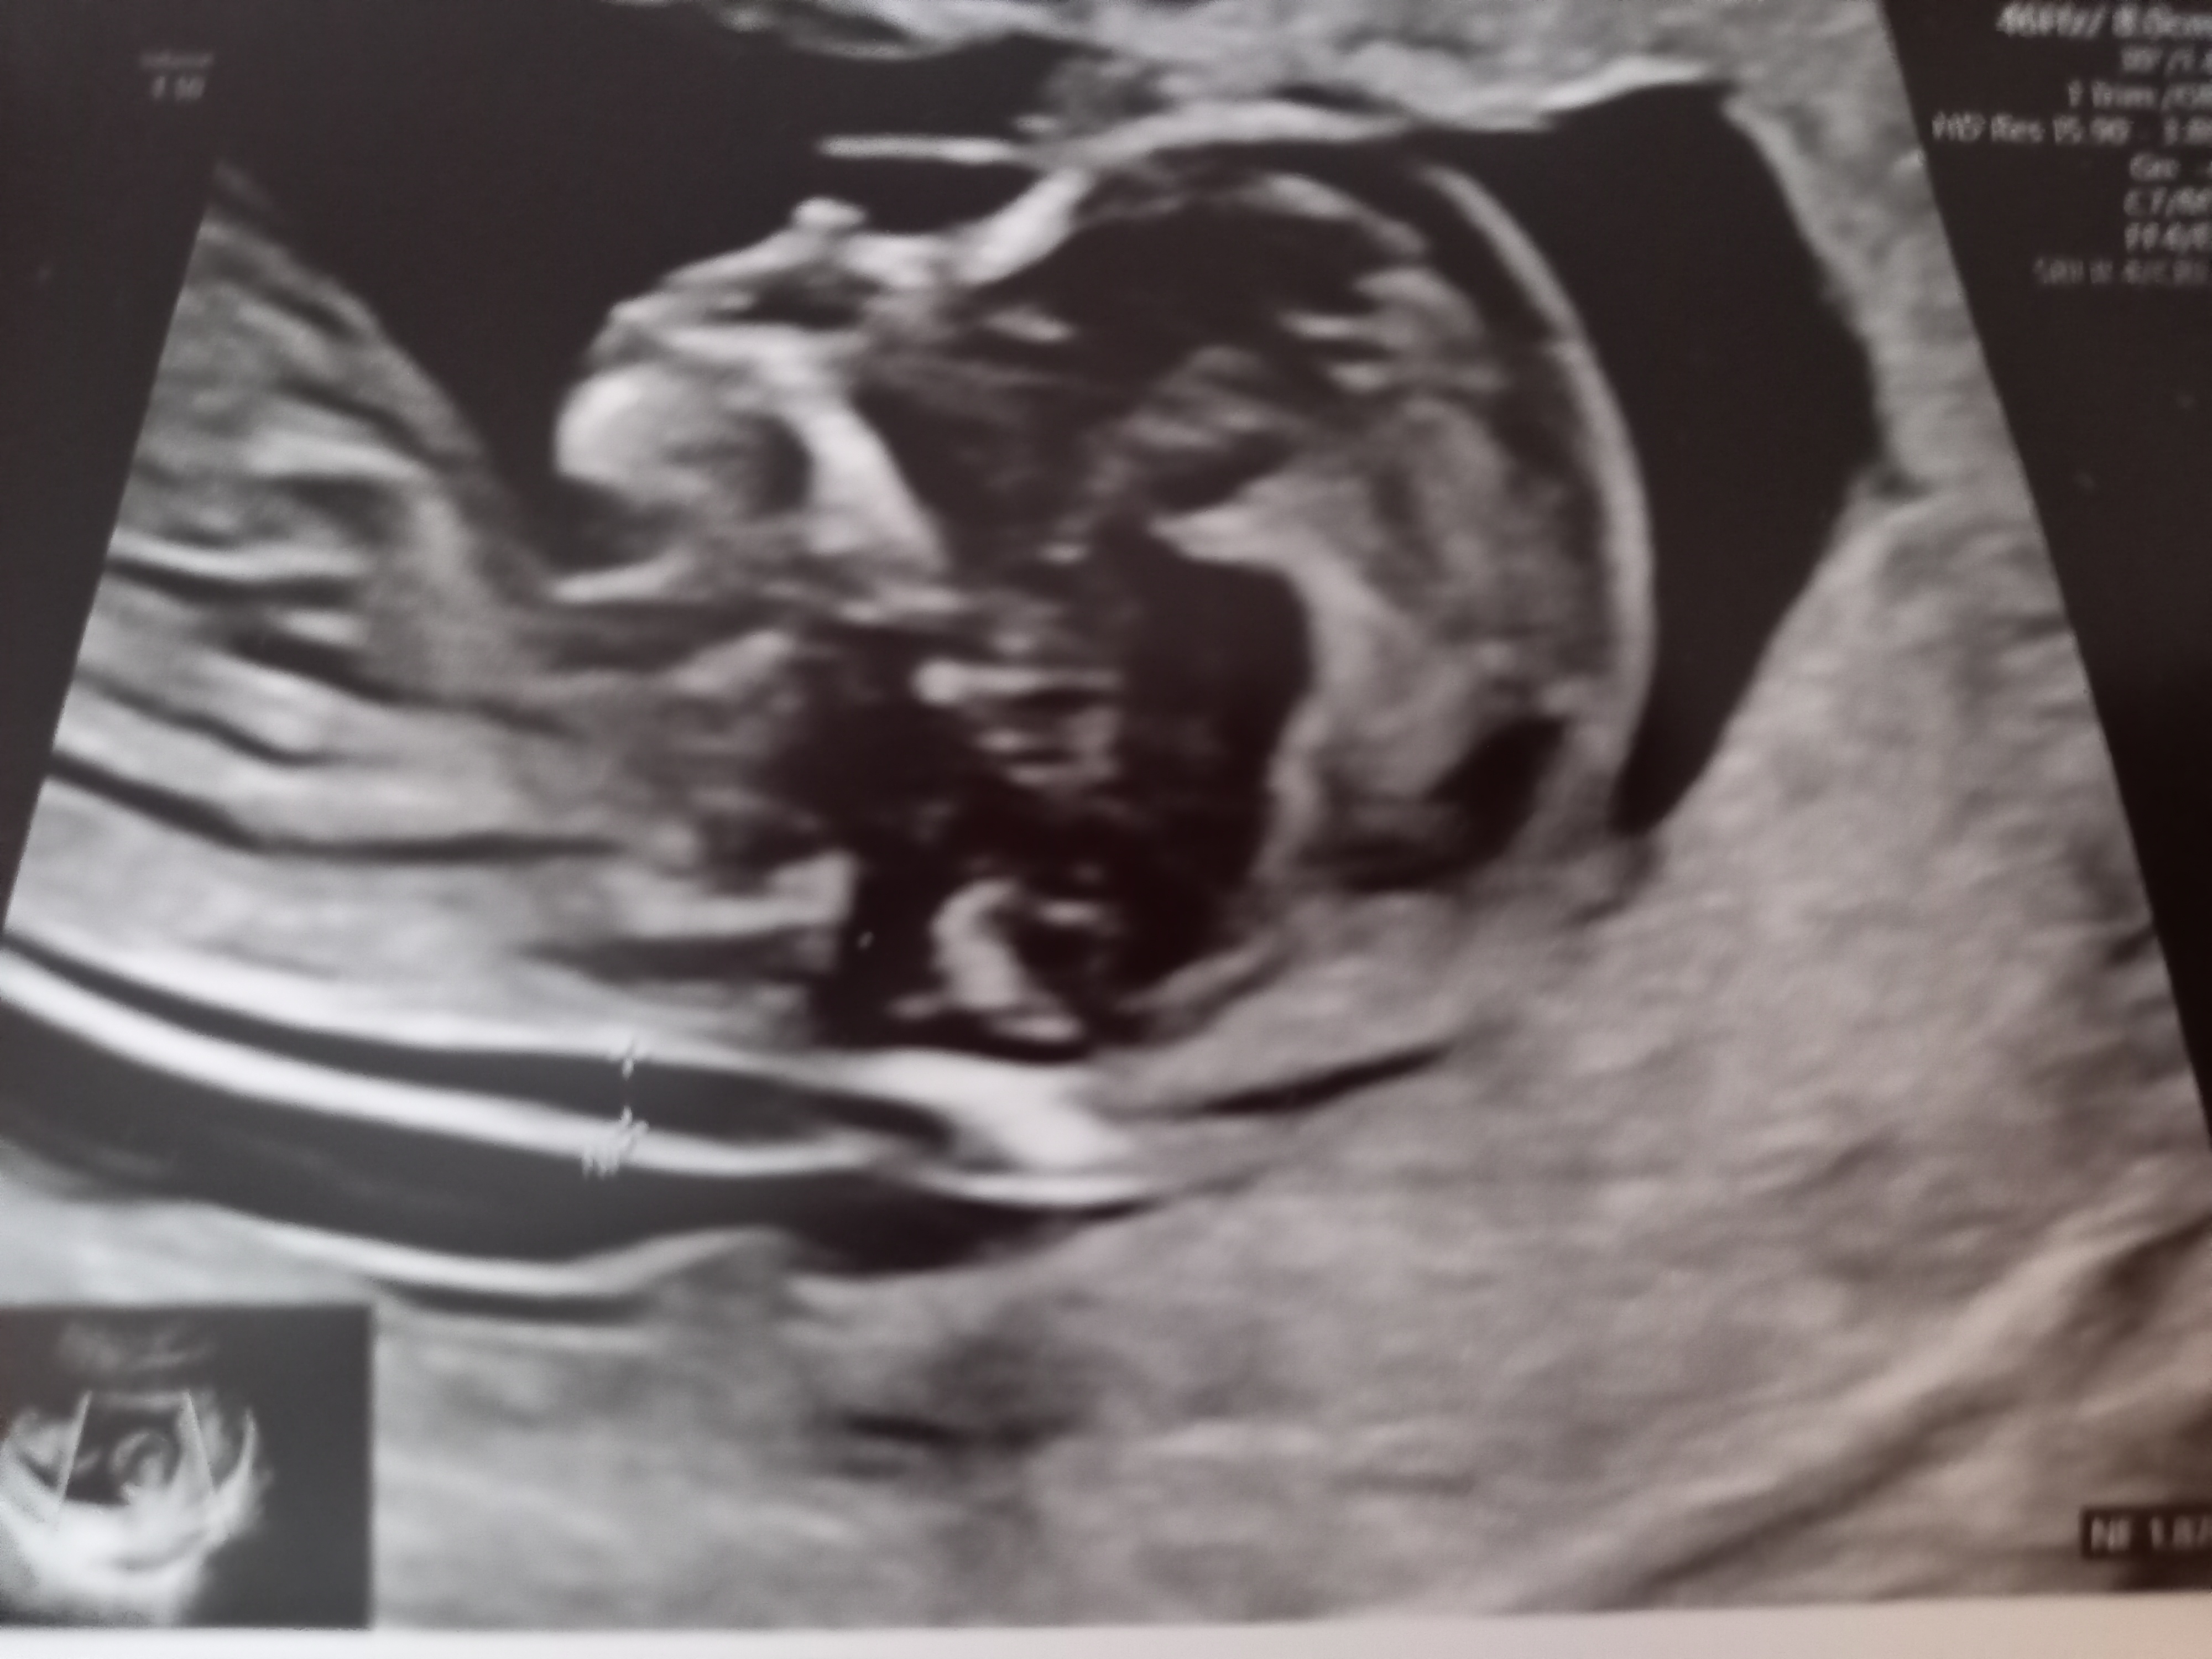

SÅ kommer vel det gøyeste, som alle har ventet på: ultralyden!

De var to stykker, hun som gjorde det meste virket som hun var under opplæring, de har jo nettopp begynt med TUL ca. uke 12 for alle nå for en måned siden. Med én gang hun satte den dingsen på magen, så vi med én gang at der var det en liten baby som bevegde på seg!

Jeg ble målt ca. like langt som jeg mener jeg er, og alt av organer osv. var akkurat som det skulle være

Vis vedlegget 389512 Vis vedlegget 389513 Vis vedlegget 389514